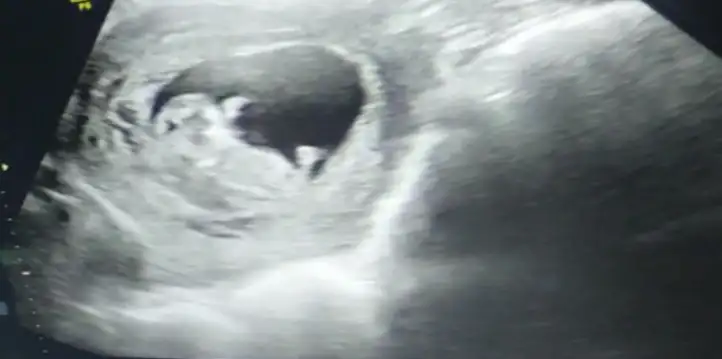

Selisay merhaba bana da bakabilir misiniz 9 hafta karından

• 8622DF24-6BCA-4DC7-B8A8-60B959D075E9.webp

44,2 KB · Görüntüleme: 90